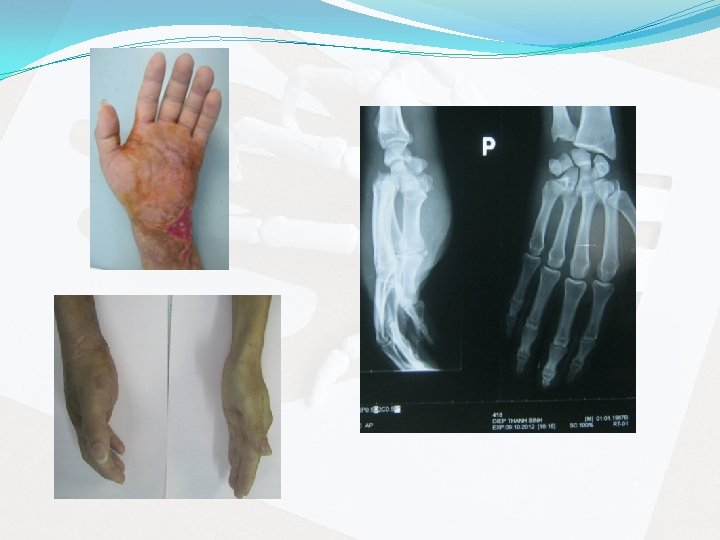

CA L M SÀNG 2: BN Mai V C. Nam, 32 t, Làm ruộng Té xe máy, CT tay T + chân P BV khác mổ KHX chân P + nẹp bột tay > 1, 5 th BVCTCH Dày bàn tay T Tê nhẹ đầu ngón Hạn chế vận động cổ tay, bàn tay Sức nắm (P) 30 kg, (T) 4 kg

Chẩn đoán trước mổ: gãy trật cũ khớp cổ tay – bàn tay II, IV, V; vỡ bờ sau x móc, cả, trật x thê, gãy nát nền x bàn I tay (T) 1, 5 tháng. Điều trị: Mổ nắn trật, xuyên kim, khâu dây chằng, nẹp bột cẳng bàn tay (P).

Hậu phẫu: 4 tuần tháo nẹp bột Tập VLTL 3 tháng Làm việc sau 4 tháng Rút kim sau 1 năm Chức năng: - ROM: gập cổ tay hạn chế - Sức nắm (P) 30 kg, (T) 20 kg (giảm 33%) - Hài lòng 8/10 - Chỉ số Mayo Clinic: 75/100 Kết quả chung: Khá